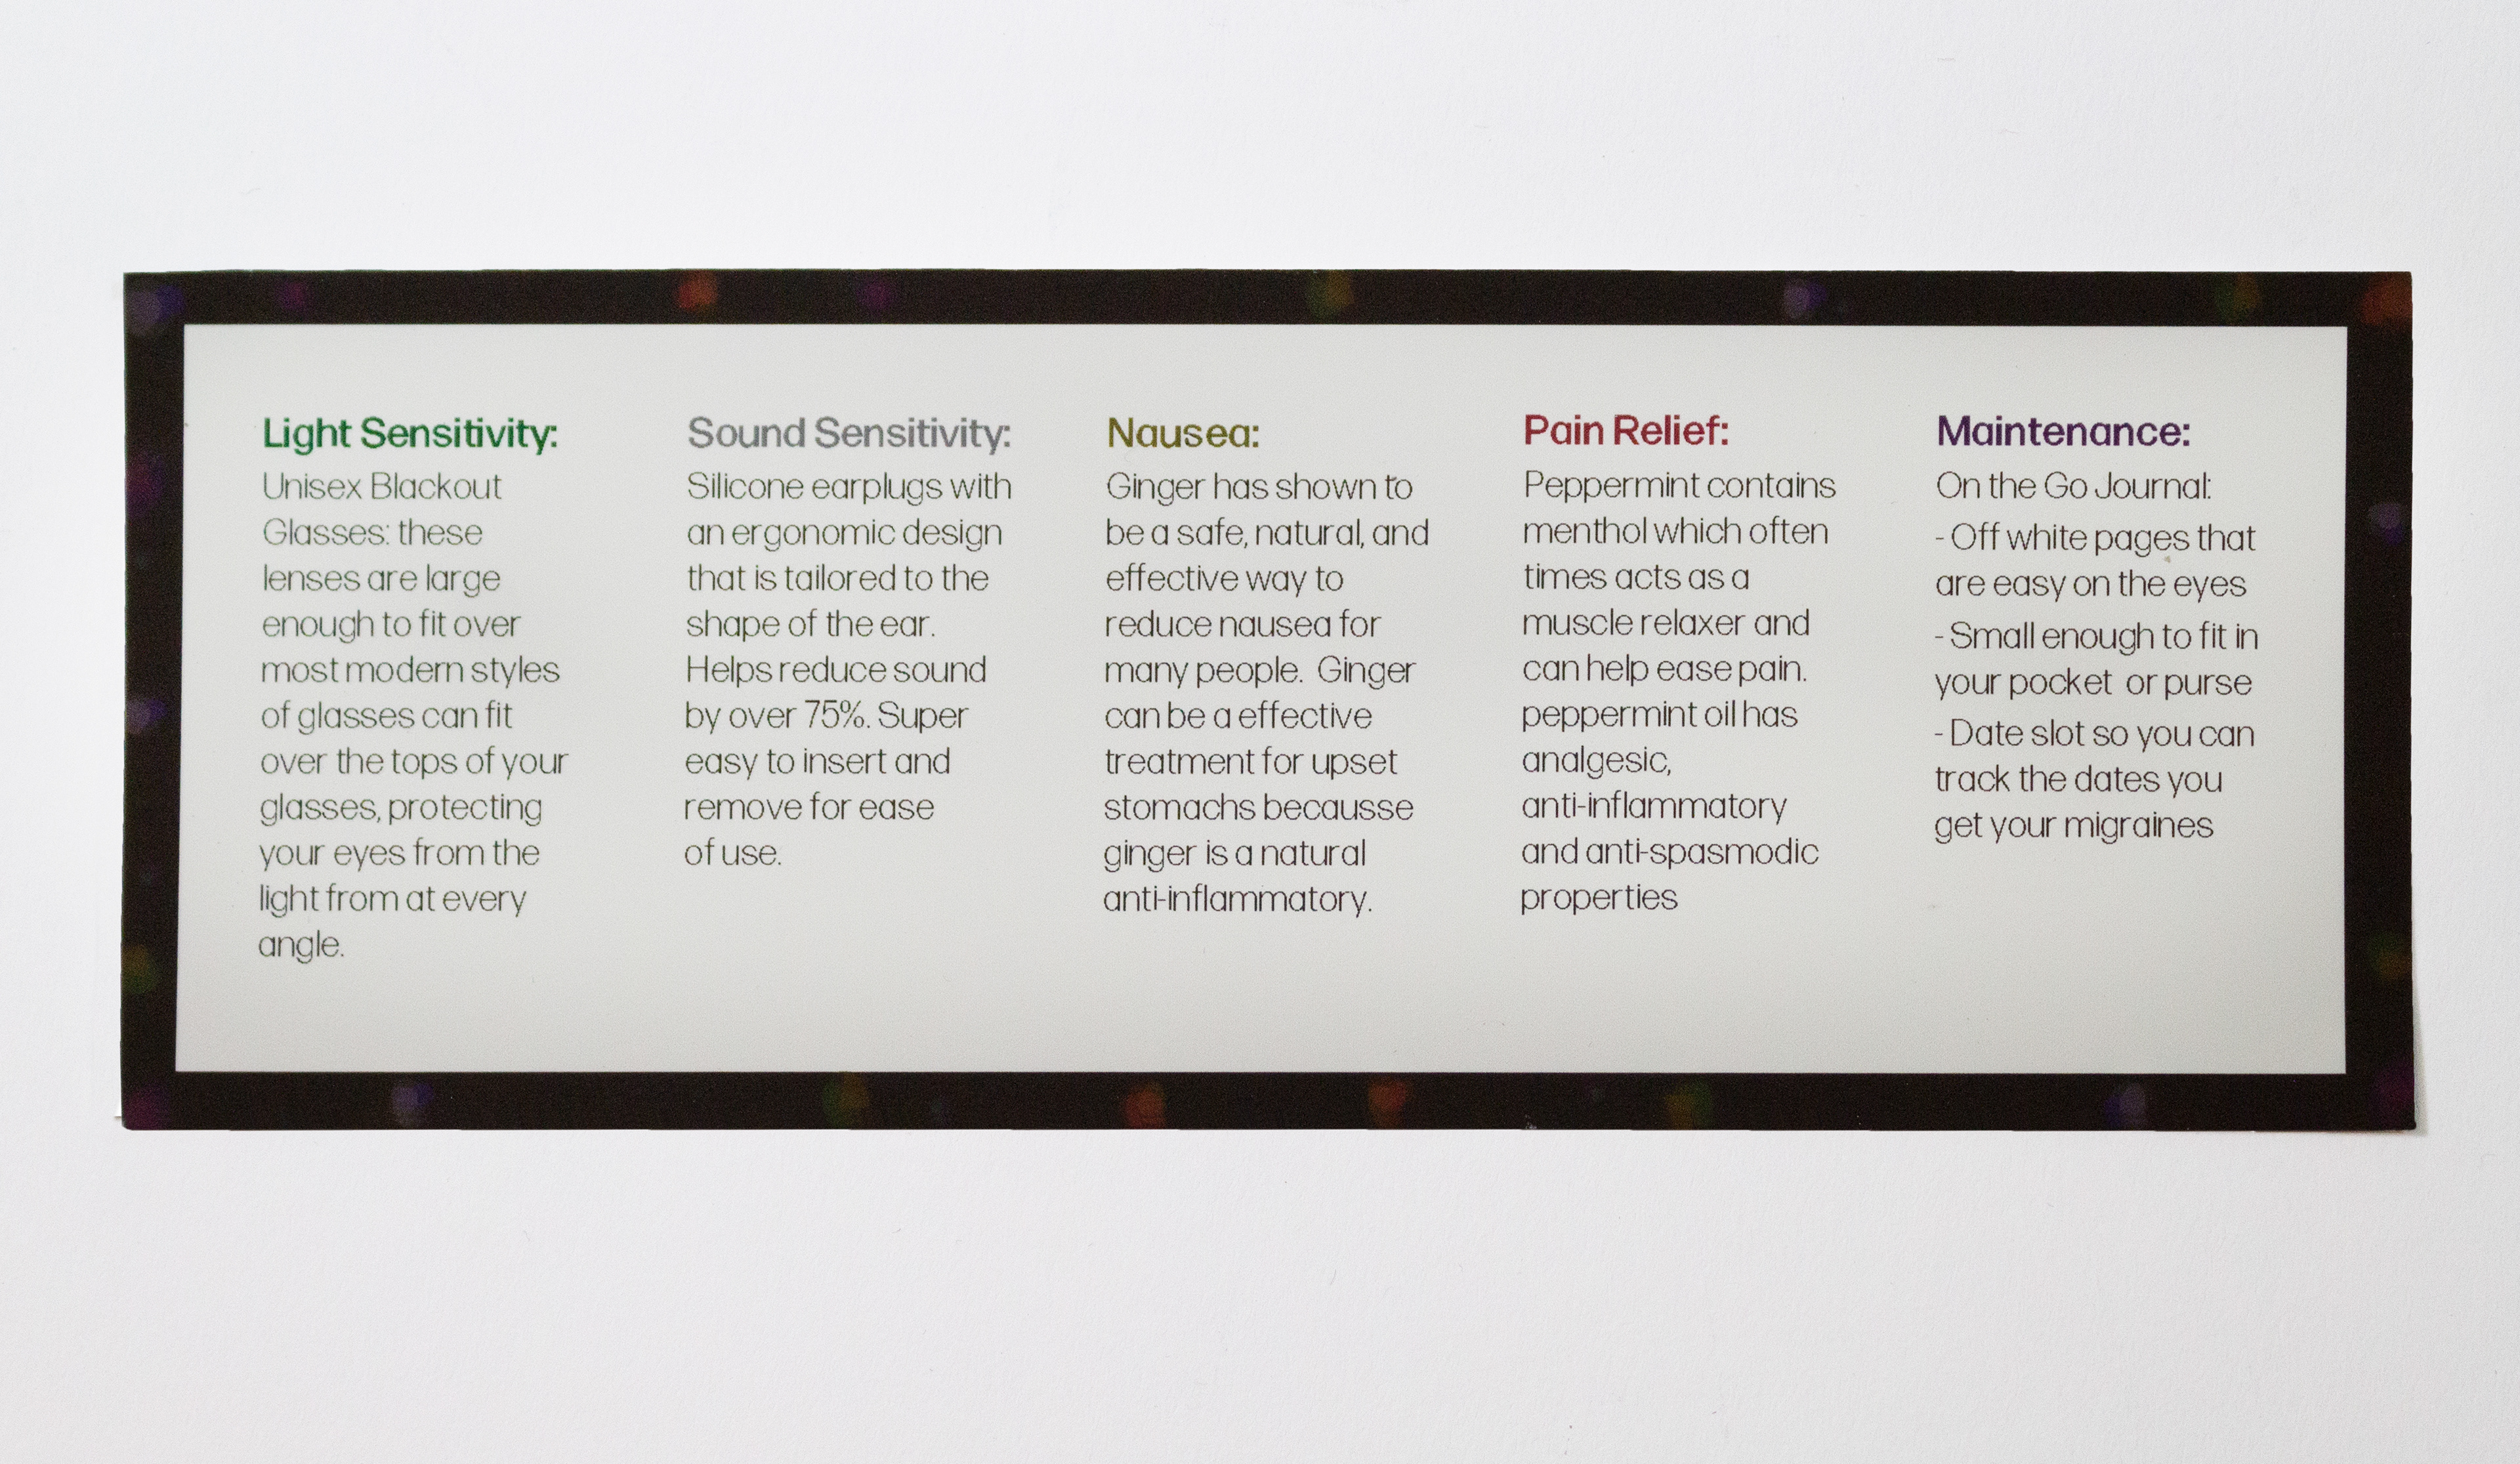

Migraine Pack Explanation Card (Front)

Migraine Pack Explanation Card (Back)

The Migraine Pack is a different approach to dealing with migraines. This box isn't trying to solve the medical problem, but is offering simple and low-cost solutions to the symptoms that someone may experience. Two types of candy are included, Ginger candy (for nausea), Peppermint candy (muscle relaxer), blackout sunglasses (for light sensitivity), earplugs (for sound sensitivity), and a small pocket size journal so you can track when and how you experience your migraines.